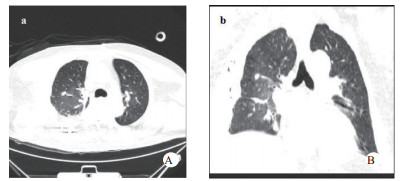

1 资料与方法患者,男,63岁,因“车祸致呼吸困难1 d”入院。既往体健。患者于2019年9月30日翻车致胸部挤压性创伤,伤后出现极度呼吸困难,送至当地医院,测血压80/50 mmHg(1 mmHg=0.133 kPa),胸部CT提示右侧血气胸,给予输血补液、去甲肾上腺素维持血压,经鼻气管插管呼吸机辅助通气,放置胸腔闭式引流管2根。因循环及氧合维持困难,10月1日转至徐州医科大学附属医院,收入EICU。入院查体:T 36.7℃,P 152次/min,R 14次/min(机械通气支持),BP 110/67 mmHg[去甲肾上腺素0.5 μg/kg·min)维持]。处于镇静状态,双侧瞳孔等大等圆,直径约2.0 mm,对光反射未引出;全身多处皮肤软组织擦挫伤,颈部及前胸、上肢广泛皮下气肿,右侧胸壁显著塌陷,反常呼吸,听诊双肺呼吸音低;心率快、心律齐、心音不遥远;腹部无异常体征;2根胸腔闭式引流管引流通畅。入院当天CT检查显示:双侧肋骨骨折伴右侧胸壁塌陷,两肺挫伤、创伤性湿肺,右肺撕裂伤,右侧液气胸,双侧胸壁广泛皮下气肿(图 1:A, B, C);未见颅内出血及腹部器官损伤。入室后0.5 h血气分析:pH 7.18,PCO2 57.5 mmHg,PO2 67.1 mmHg,Lac 4.4 mmol/L,氧合指数67.1 mmHg,APACHE Ⅱ评分27分。治疗上予镇痛镇静、保护性肺通气策略、保温、预防感染等治疗,效果不佳,连枷胸,皮下气肿范围不断扩大,氧合指数持续<100 mmHg。于10月2日气管切开后行V-V ECMO治疗(右股静脉—右颈静脉);因右侧血胸、胸引量24 h达1 000 mL,血红蛋白下降,凝血功能显著异常,存在创伤性凝血病,采取无肝素抗凝ECMO技术,提高血流速(4.6 L / min),气流速(5 L / min),FiO2 100%;给予成分输血,监测ACT及APTT。ECMO转机1h后去甲肾上腺素停用,复查血气分析PO2 105 mmHg。此后,患者氧合和血流动力学逐步改善,创伤性凝血病已纠正,于10月7日在无肝素V-V ECMO支持下行“胸骨骨折切开复位钢板内固定术+右侧3、4、5前肋肋骨骨折环抱器内固定+右侧5、6、7、8后肋肋骨骨折环抱器内固定术+两侧胸腔闭式引流术”。术中见第5肋骨前端骨折向下外移位,3、4肋骨多段骨折,胸壁前上方完全塌陷,肺脏直接外露,胸腔内布满血凝块,术中取出血凝块共约1 000 mL。术后氧分压上升至400 mmHg,术后复查床边胸片,肺部影像学较前改善(图 2 A, B),继续无肝素V-V ECMO治疗1 d后,于10月8日开始肝素抗凝,维持ACT在160 s~180 s,APTT在40 s~50 s,肝素化期间无出血并发症发生。10月11日行自主氧合试验通过,予以撤机。10月12日复查胸部CT两肺复张满意(图 3 A, B),开始间断停用呼吸机并床边康复训练。10月28日撤离呼吸机,气切处高流量吸氧。11月15日拔除气切管。11月18日康复出院,无明显并发症发生。

| 图 1 A胸部CT纵隔窗(右侧胸壁塌陷);B胸部CT肺窗(广泛皮下积气,肺挫伤);C肋骨三维重建(多根多处肋骨骨折)。 |